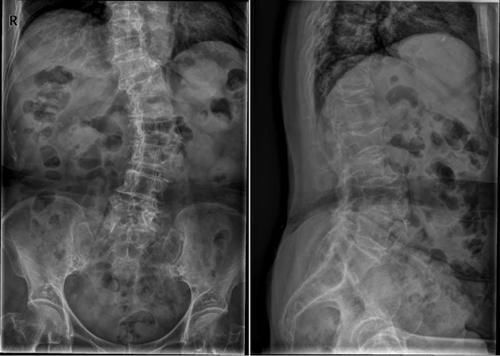

Case13:F,4y;腰痛1月余,加重半月。

文章插图